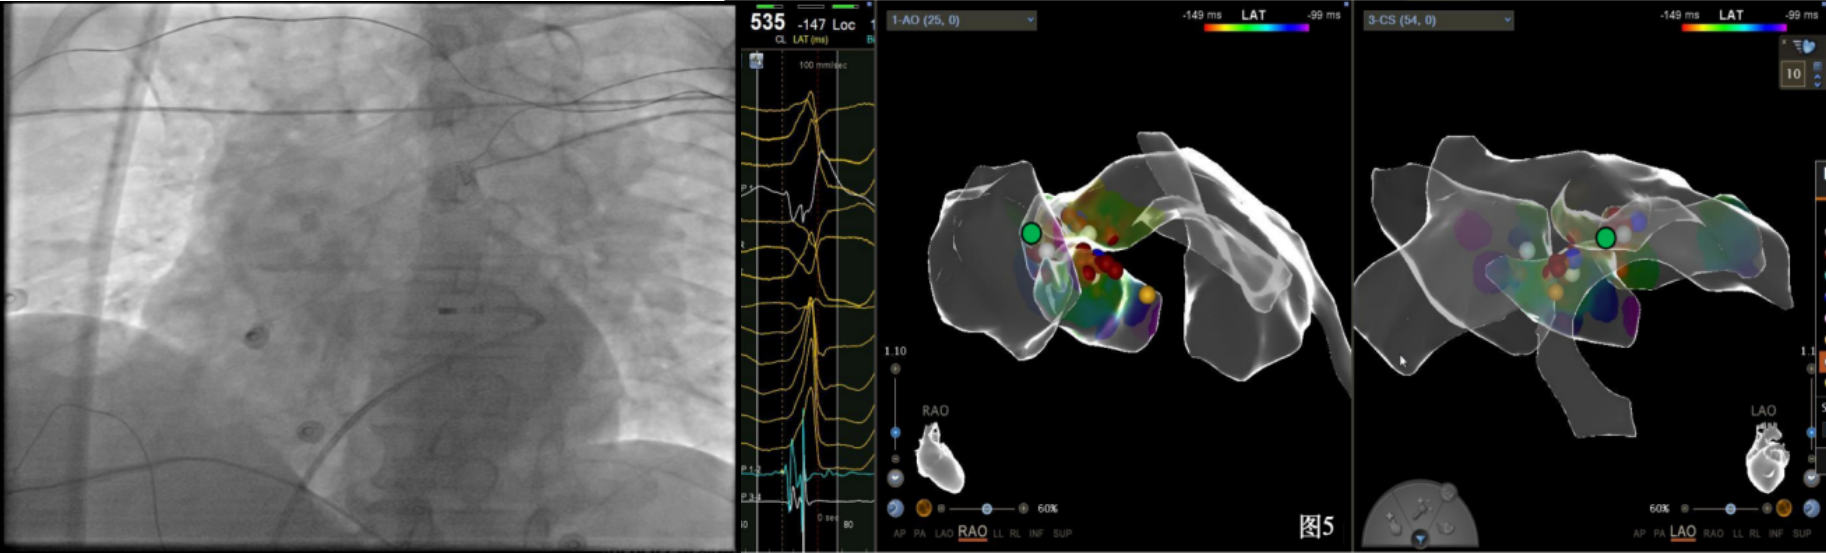

手术中,周明礼团队凭借其丰富的临床经验和精湛的技术,穿刺右股动脉后,将消融大头顺利送入主动脉,于主动脉瓣上标测到最早点(图3红色点)领先体表8ms,电位不理想,果断去到主动脉瓣下左室穹顶部标测,标测到最早点(图4白色点)领先体表25ms,放电消融3s,早搏消失,消融90s后观察2min后,早搏恢复,在该有效点周边补充消融,早搏依旧未能消失,考虑起源点较深,内膜消融未能透壁损伤到起源,随

即穿刺股静脉,将消融大头送至冠状窦内,在GCV远端对应位置标测到最早点(图5绿色点)领先体表27ms,消融后早搏未能消失,周明礼评估起源点偏心外膜,能量依旧不能穿透损伤到起源点,内膜消融基本无效后,果断选择难度系数最为复杂的干性心包穿刺心外膜消融。在导丝的指引下,将消融大头送至心包层(图6),于外膜标测到靶点(图7黄色点)电位领先体表31ms,单极电位无r波且有顿挫,ssummit外膜离冠状动脉较近,比较危险,保证安全,进行了冠脉造影(图7),显示距离LAD和LCx有一定距离,相对安全,随即放电,2s室早消失,10s患者出现心率变慢,该区域走形迷走神经节,消融导致心率减慢,随后保证心率正常的情况下,消融够60s,随后观察半小时,早搏没有恢复,手术成功(图8)。经过不懈的努力,患者恢复了窦率,心脏功能也逐渐恢复正常,手术取得了圆满成功。